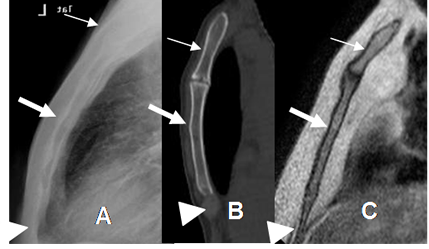

El esternón es un hueso plano, con leve convexidad anterior. Está dividido en 3 partes: El mango o manubrio, el cuerpo y la apéndice xifoides. (2). (Fig 3).

Fig 3. Esternón normal.

A: Rx lateral. B: TAC reconstrucción sagital y C: RM sagital en T1. Esternón normal. Manubrio (Flecha delgada), cuerpo (Flecha gruesa) y apéndice xifoides. (Punta de flecha).